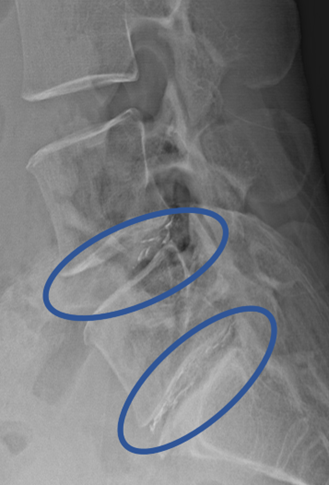

DiscoGelを入れた後の画像になります。